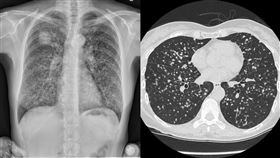

手指頭變「杵狀指」 權威醫:是肺癌警訊

肺癌已經成了台灣癌症發生率、死亡率的雙冠王。肺癌初期...

沒理健檢報告3年後肺癌 醫:倒數計時了

別忽視身體發出的警訊!胸腔科醫師蘇一峰今(21)日指...

手變形成「杵狀指」 權威醫:是肺癌警訊

據衛福部國健署公布的數據顯示,台灣平均每44.7分鐘...